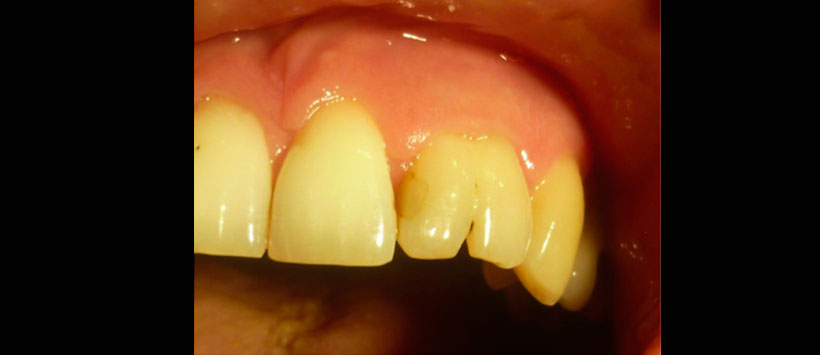

El paciente no presenta patologías de base, ni antecedentes de trauma bucal ni facial. Al examen físico se observa geminación de pieza 2.2, la cual presenta una restauración mesial (Figura 1) y aumento de volumen fluctuante levemente doloroso en el tercio anterior del paladar duro, con leve abombamiento de la tabla ósea vestibular.

A los tests de sensibilidad, solo es positivo para percu- sión, y es sensible a la palpación periapical. No hay cambios de color coronario, y los exámenes térmicos y eléctricos son negativos. Se solicitan radiografías convencionales, en las que se observa una imagen radiolúcida extensa de lími- tes netos no corticalizada, en relación a piezas 2.1, 2.2 y 2.3. Se complementa con tomografía computarizada Cone Beam (CBCT) (Figura 2), mostrando una imagen compatible con quiste radicular inflamatorio en pieza 2.2. Sus mediciones son 20 mm mesio-distal, 13 mm vestíbulo-palatino y 11 mm céfalo-cauda. Posterior al tratramiento, se le realizo una tomogriafia de control a los 20 meses para evalular el estado del tratamiento endoodntico asi como la cirugia.(Figura 3)